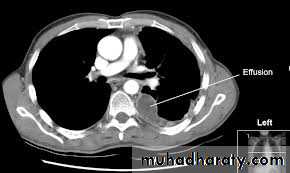

-CT displays pleural abnormalities more readily than either plain radiography or ultrasound, and may distinguish benign from malignant pleural disease